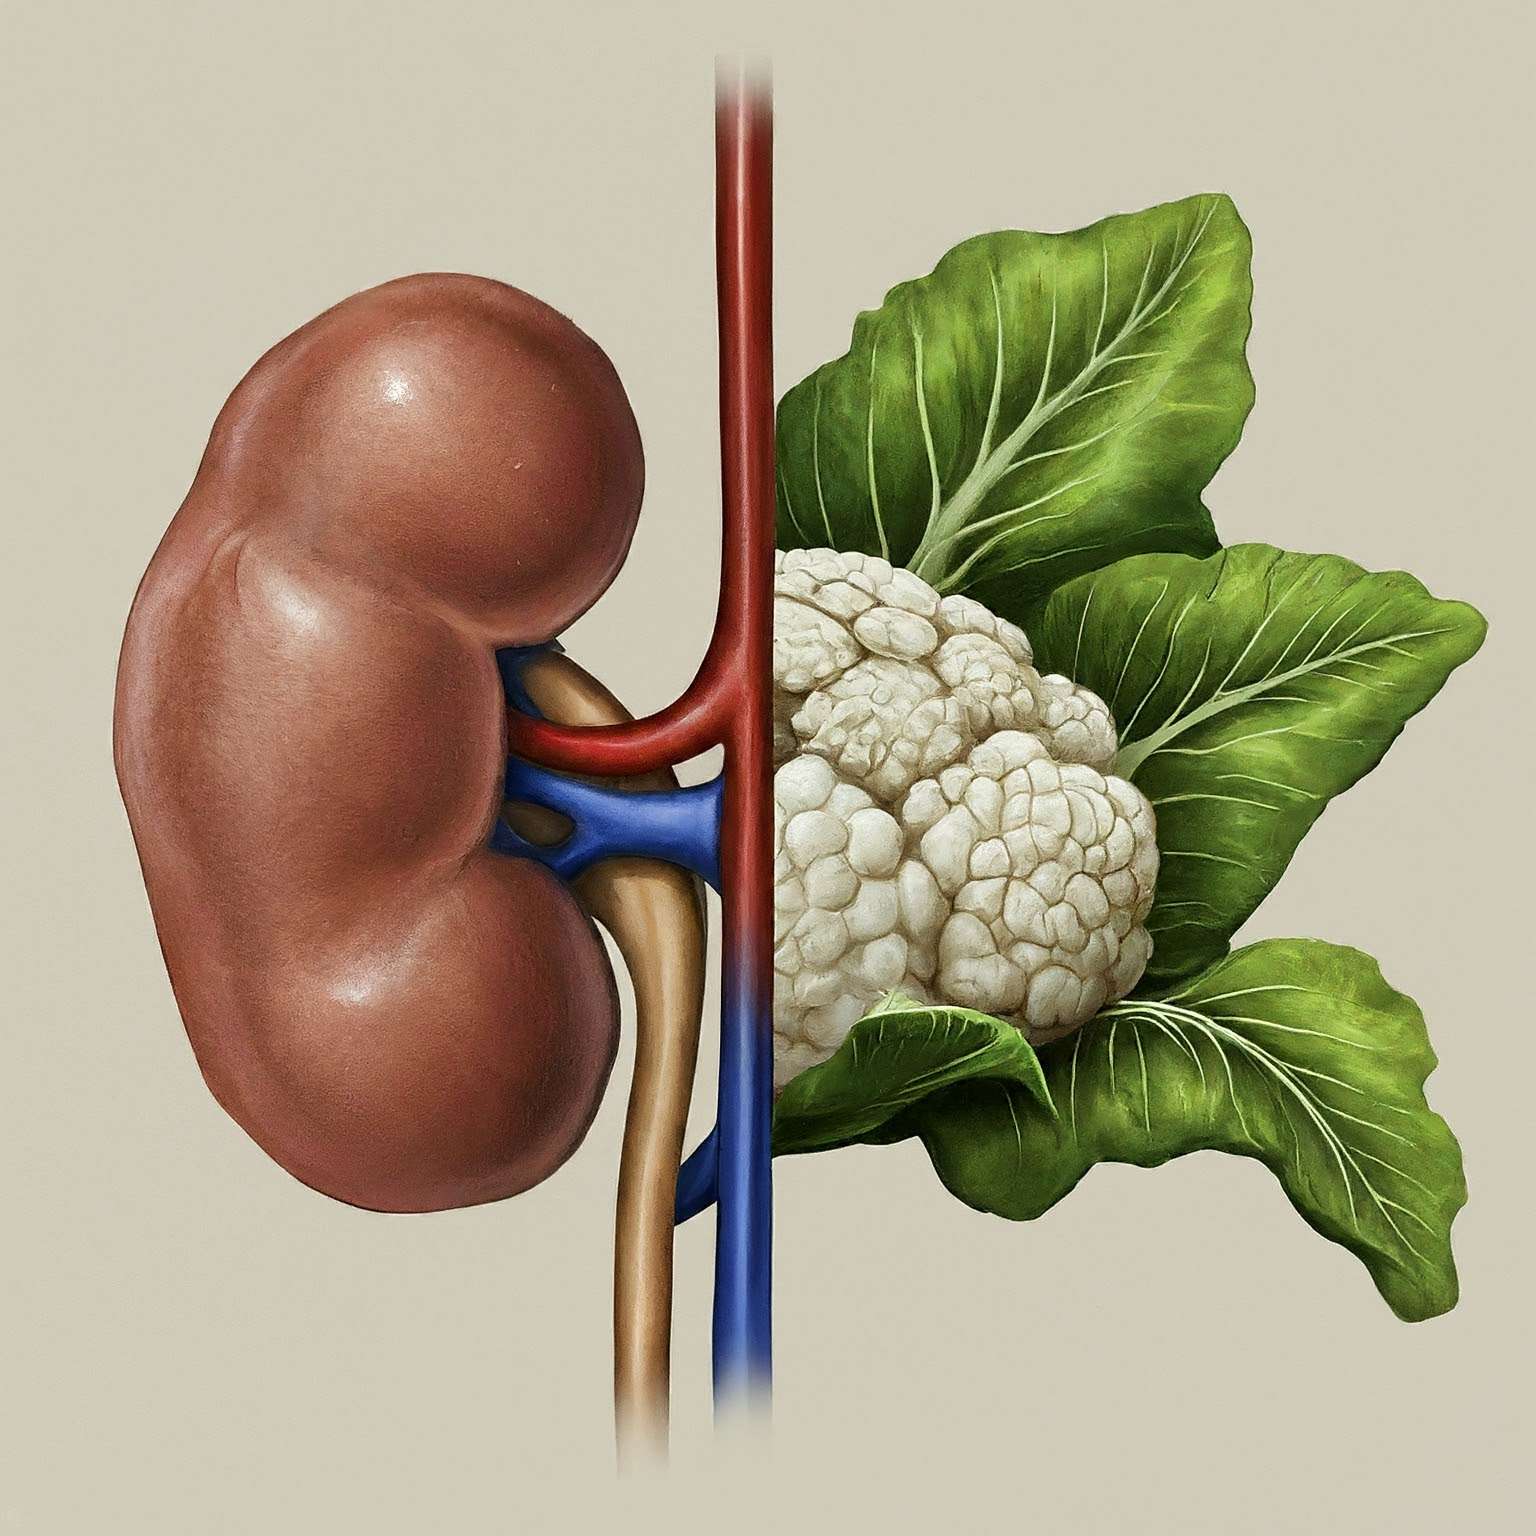

Green vegetables have taken the health world by storm, lauded for their vitamin and antioxidant content. But whispers of caution linger – could these leafy wonders harm your kidneys? The answer, like most things in life, isn’t a simple yes or no. Let’s delve into the truth – green vegetables can be a boon for healthy kidneys, offering essential nutrients and potentially supporting their function. However, for those with existing kidney problems, potassium, abundant in some greens, can become a concern. Don’t ditch the kale just yet! By understanding the potential downside and consulting a healthcare professional, you can enjoy these nutritional powerhouses while keeping your kidneys happy. Stay tuned as we explore the good, the not-so-bad, and how to strike a healthy balance for your kidneys!

Transitioning to a kidney-friendly diet can initially evoke feelings of apprehension and uncertainty. However, beyond the confines of restrictive eating lies a world of culinary exploration and nourishment. Understanding the fundamental principles of a kidney-friendly diet empowers individuals to make informed dietary choices while optimizing kidney function. It’s essential to challenge misconceptions and fears surrounding dietary restrictions, recognizing that embracing a kidney-friendly lifestyle is not about deprivation but rather about nurturing and supporting renal health. By adopting practical strategies such as meal planning, seeking professional guidance, and fostering a positive relationship with food and health, individuals can navigate their journey with confidence. Ultimately, this journey is not just about managing kidney health but also about embracing a holistic approach to well-being, fostering resilience, and celebrating the victories, no matter how small, along the way.